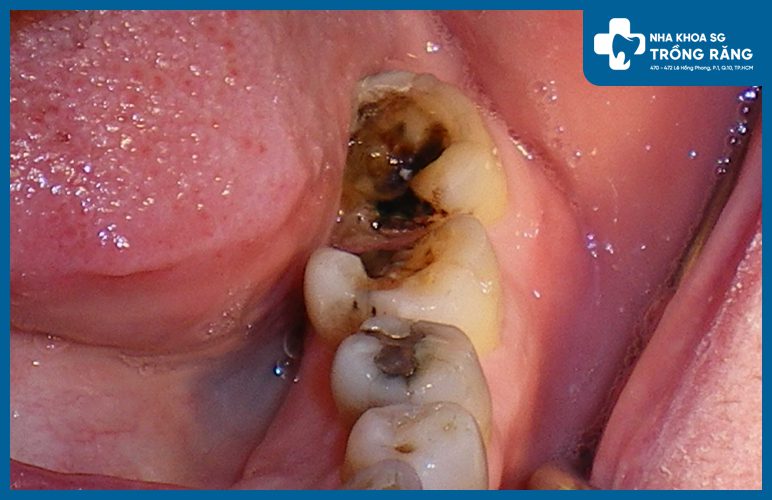

Đau răng hàm do men răng bị mòn hoặc bên trong răng bị viêm kích thích lên dây thần kinh dẫn đến tình trạng đau vùng hàm mặt. Nhiều trường hợp răng đau dữ dội ở răng hàm trong cùng, xuất hiện dọc hàm trên và hàm dưới kèm theo triệu chứng đau răng hàm và đau đầu, hay đau răng hàm và đau tai. Đó chính là “tín hiệu” từ cơ thể cảnh báo răng của chúng ta đang bị tổn thương và cần được điều trị. Đặc biệt là viêm tủy răng.

Những nguyên nhân tiềm ẩn gây ra đau răng hàm, bao gồm:

- Sâu răng

- Viêm tủy răng